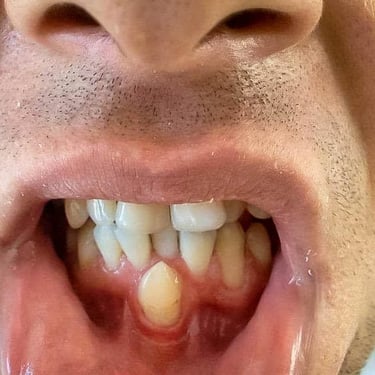

Dientes impactados

Los dientes impactados son dientes que no pueden erupcionar correctamente debido a la falta de espacio o a una obstrucción.

Los pacientes pueden notar que un diente no ha salido, aunque debería haberlo hecho. Esta condición es común con las muelas del juicio y los caninos superiores.

El tratamiento puede incluir la extracción del diente impactado o la creación de espacio para permitir su erupción.